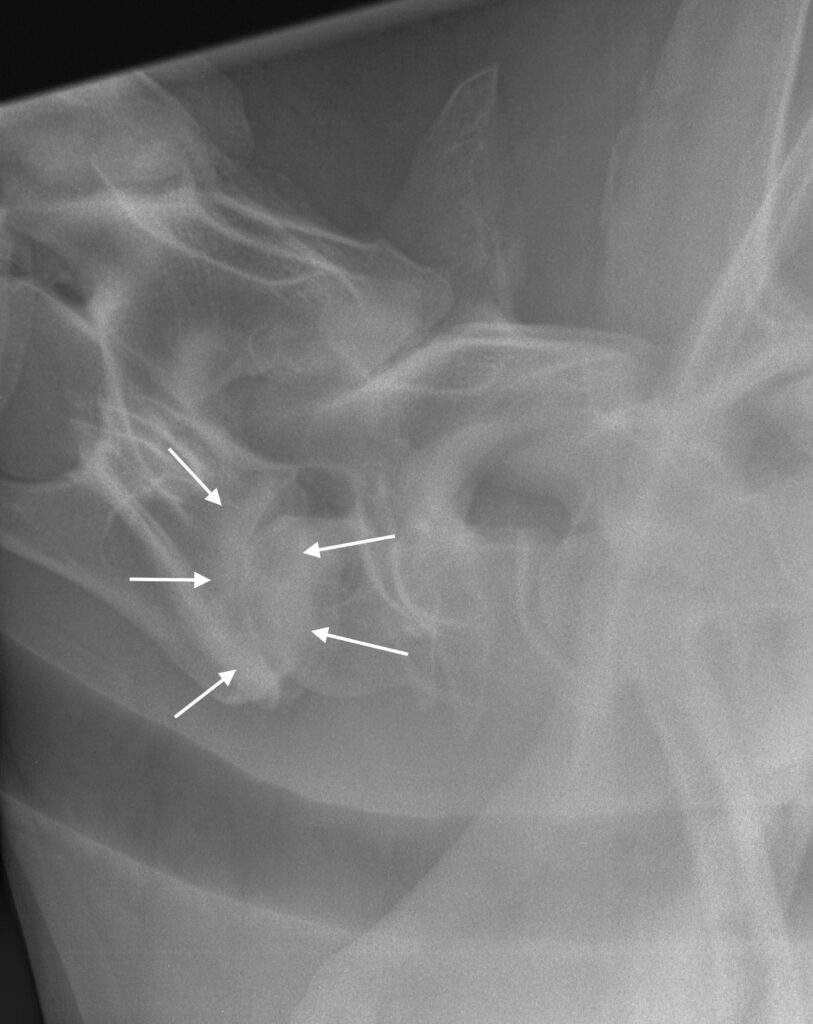

Artróza meziobratlových kloubů (obr. 7 a 8): Pokud dojde ke vzniku artrotických změn na malých kloubech mezi jednotlivými obratli, jednotlivé plošky kloubu zduří, což může vést ke zúžení páteřního kanálu.

Obrázek 7: Rentgen krku koně se závažnou artrózou na úrovni C7–T1; meziobratlová ploténka je téměř zničena a došlo ke zhroucení kloubu (bílé šipky)

Obrázek 8: Kůň na obr. 7 byl ataktický a často docházelo k blokádám krční páteře, proto byla provedena artrodéza C7–T1

Artróza v tomto místě může vzniknout jak přirozeně v důsledku stárnutí koně, tak například kvůli přítomnosti OCD fragmentů (obr. 6). Velmi často se objevují artrotické změny v kloubech krční páteře jako následek předchozího úrazu. Pokud kůň upadne přes hlavu jako roček na pastvině, je možné, že se už u tak mladého koně rozvine artróza krční páteře s nebo bez rentgenologicky detekovatelných kostních úlomků.